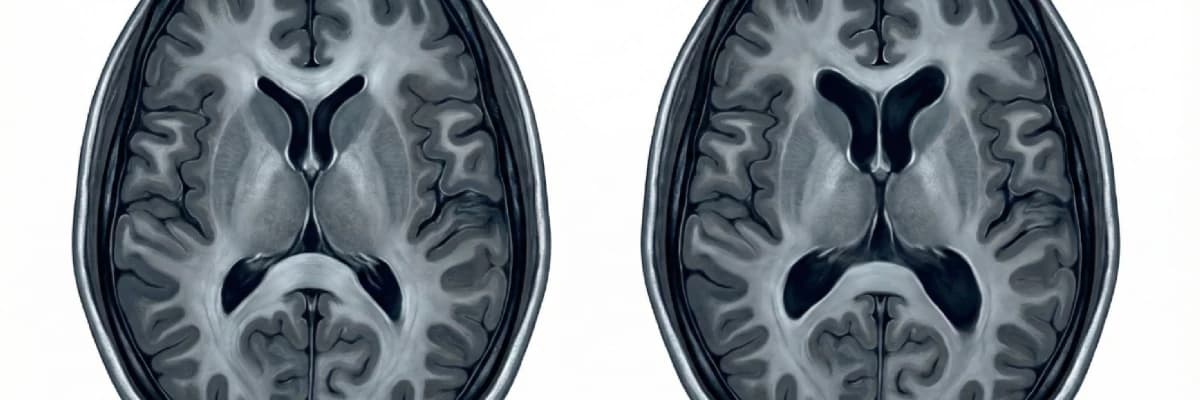

3. Her Ventrikül Genişlemesi Hidrosefali midir?

Kısa cevap: Hayır.

Hidrosefali, basitçe anlatmak gerekirse; beyin omurilik sıvısının üretimi, dolaşımı veya emilimindeki bir bozukluk nedeniyle, beyin içi sıvı boşluklarının anormal şekilde genişlemesi ve buna bağlı şikâyetlerin ortaya çıkması durumudur.

Ventriküller şu nedenlerle geniş görünebilir:

-

BOS dolaşımında gerçek bir bozukluk vardır → hidrosefali gelişmiştir.

Beyin dokusunda yaşa veya başka nedenlere bağlı atrofi (hacim kaybı) vardır; iç boşluklar bu nedenle görece daha geniş görünür → her zaman hidrosefali sayılmaz.

Bazı kişilerde yapısal/anatomik olarak ventriküller biraz daha geniş olabilir → bu da her zaman hastalık anlamına gelmez.

Bu yüzden, MR’daki ventrikül ölçüsünü tek başına okuyup “hidrosefali var/yok” demek mümkün değildir; mutlaka klinik tablo ile birlikte değerlendirme gerekir.